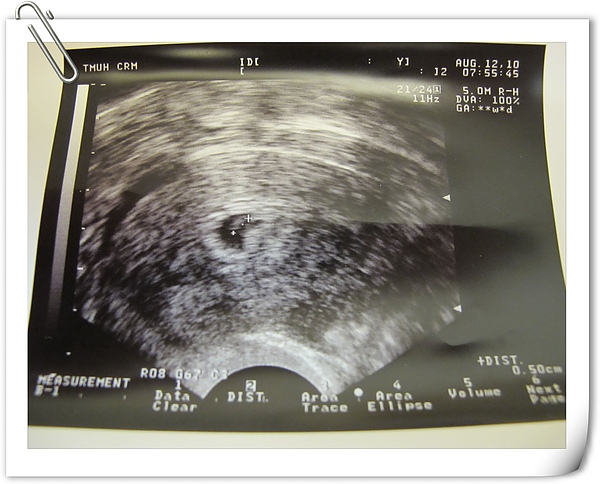

8/10

早上很早就到辦公室

同事要開會,所以請我幫忙

準備開會的東西外還弄了一桶很重的茶水